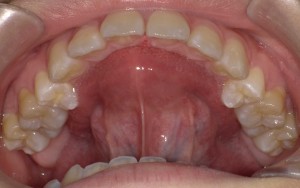

上顎前突🔸出っ歯な噛み合わせ

交叉咬合🔸上の歯と下の歯が交叉(クロス)したような噛み合わせ

開口🔸上の歯と下の歯で噛んだ際(咬合した際)に前歯が開いている噛み合わせ

舌が入る隙間があるのがわかりますか?💡

正中離開🔸前歯の1番目の歯が左右に離れる(離開する)

の原因となる事があります🦷